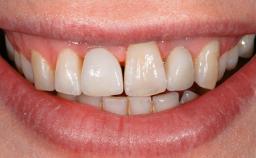

A 73-year-old woman was referred to the Division of Periodontology (University of Geneva School of Dental Medicine) after repeated unsuccessful treatment of a peri-implant infection. She was systemically healthy and did not smoke. The patient’s history revealed that, three years earlier, an immediate implant (Straumann Tapered Effect RN 4.8/4.1; Institut Straumann AG, Basel, Switzerland) had been inserted to replace the upper right central incisor. A metal-ceramic crown had been delivered using an adhesive resin cement. One year later, the patient had consulted another dentist due to discomfort in the soft tissues in the implant region. There was a suppurating peri-implant pocket, 10 mm deep. Peri-implant bone loss and excess luting cement were seen on the radiograph. The situation was treated with non-surgical debridement, amoxicillin, and repeated submucosal irrigation with a chlorhexidine digluconate solution. The patient was referred after the suppuration had persisted for several months.